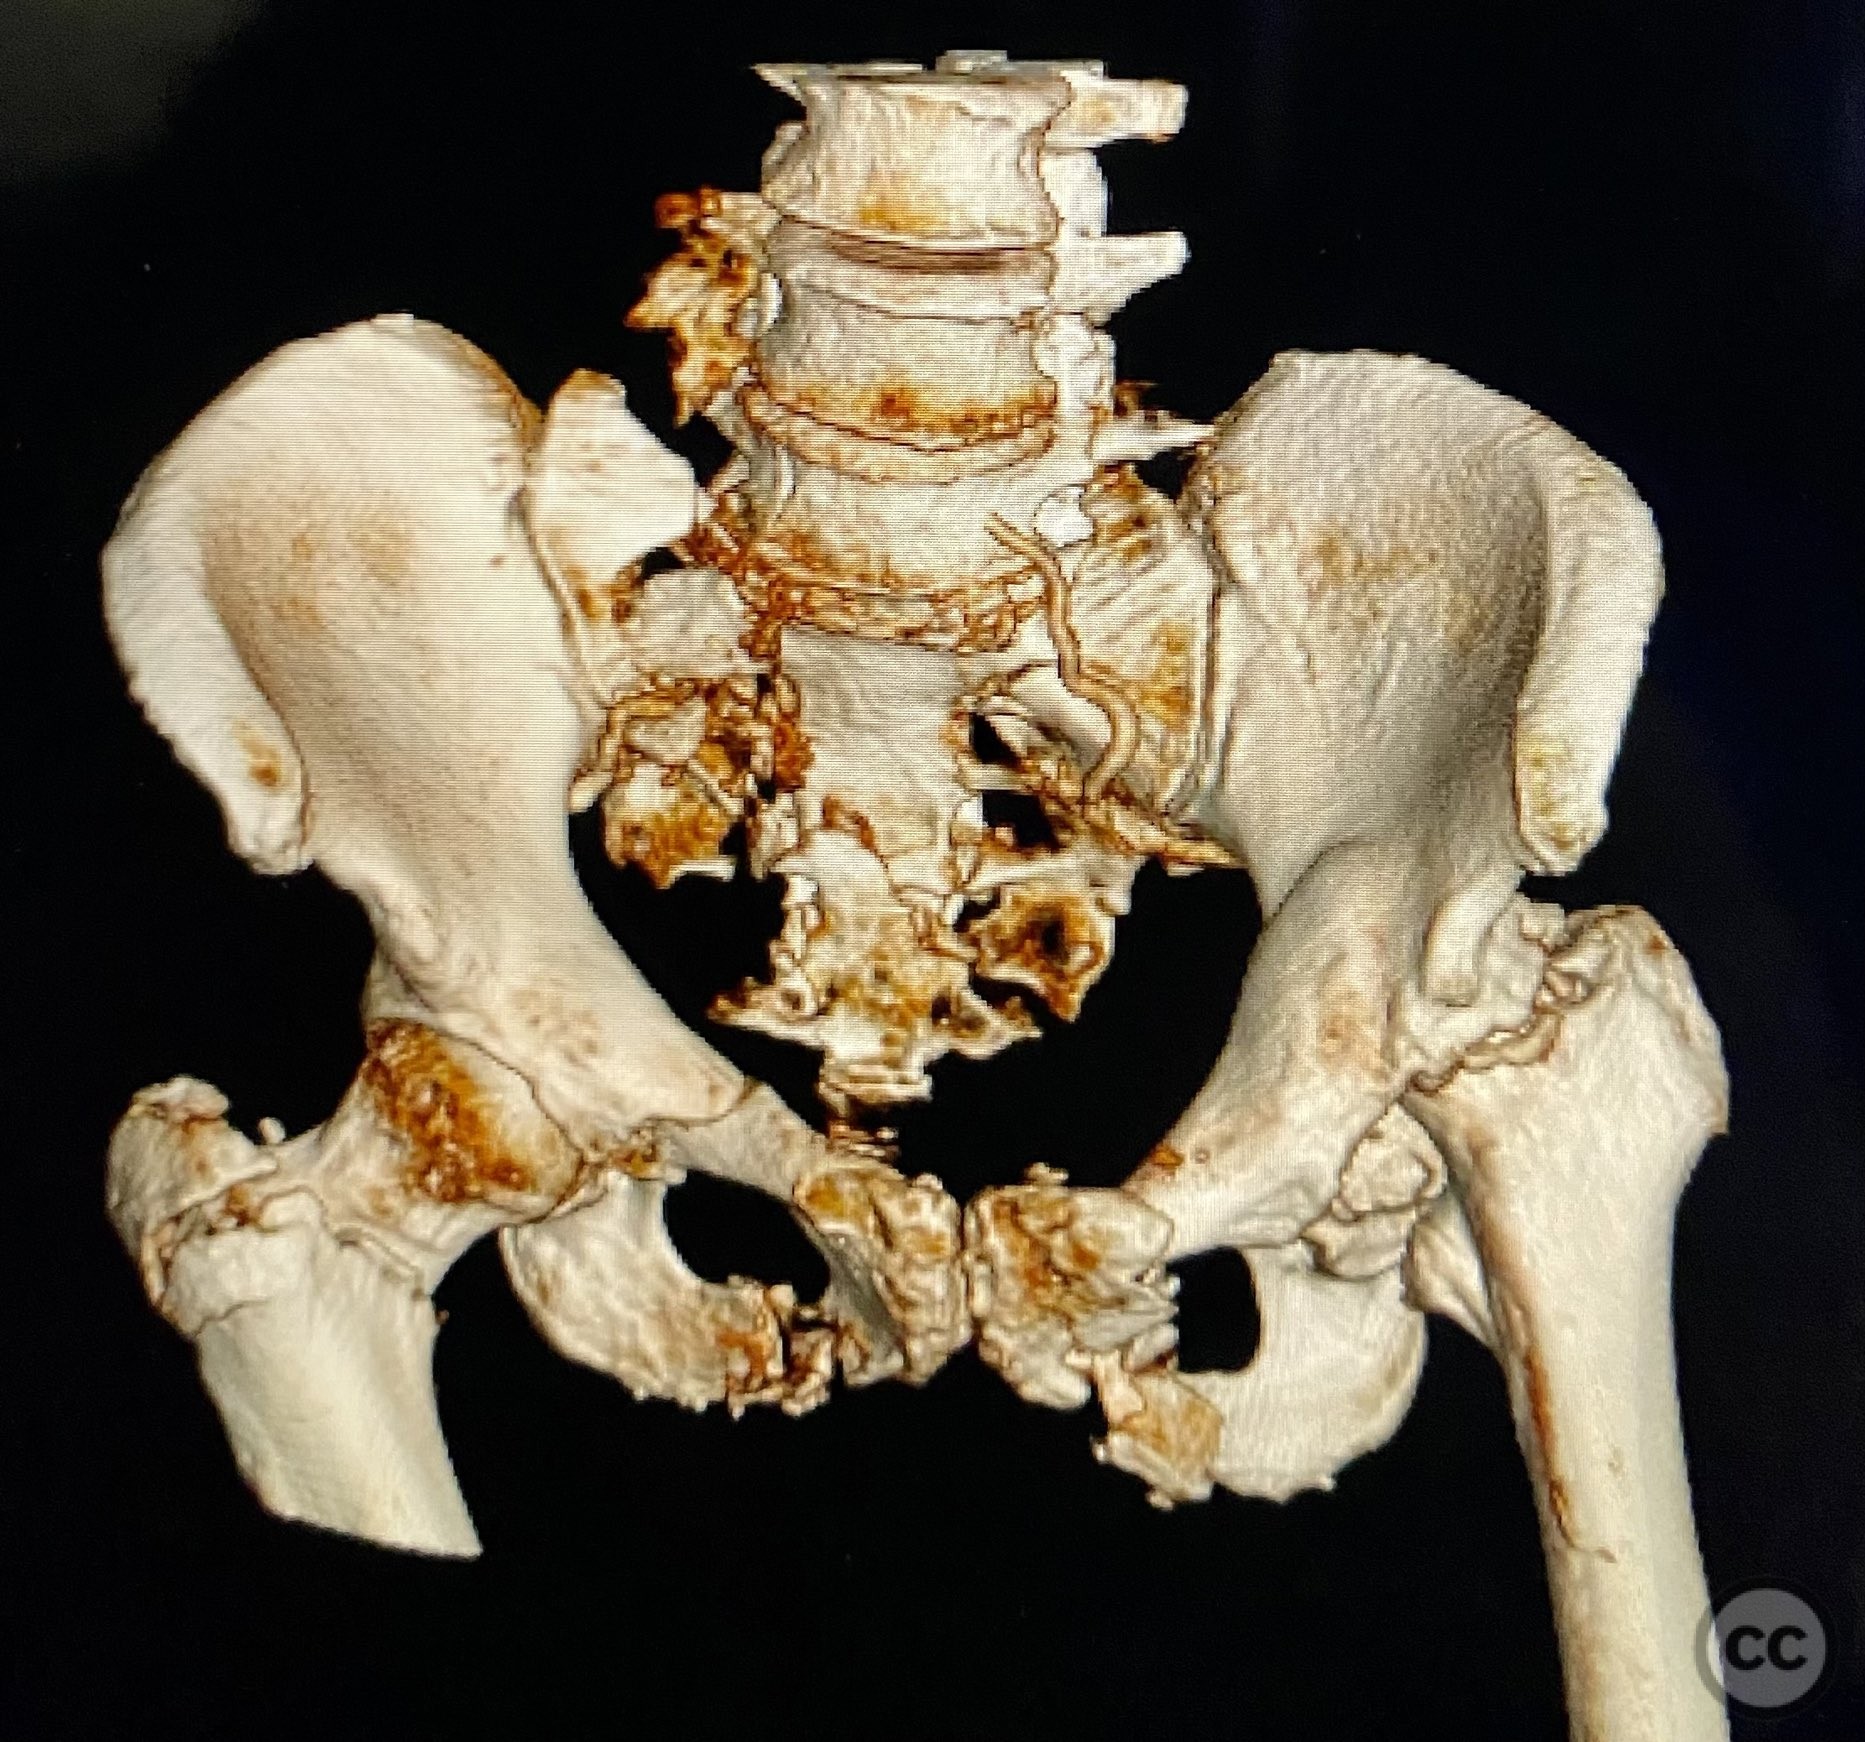

Uploaded on Sep 12 2025

Combined Bilateral Sacroiliac Disruption and Tra...

• Case by Chip Routt

Specialist Consultant - United States